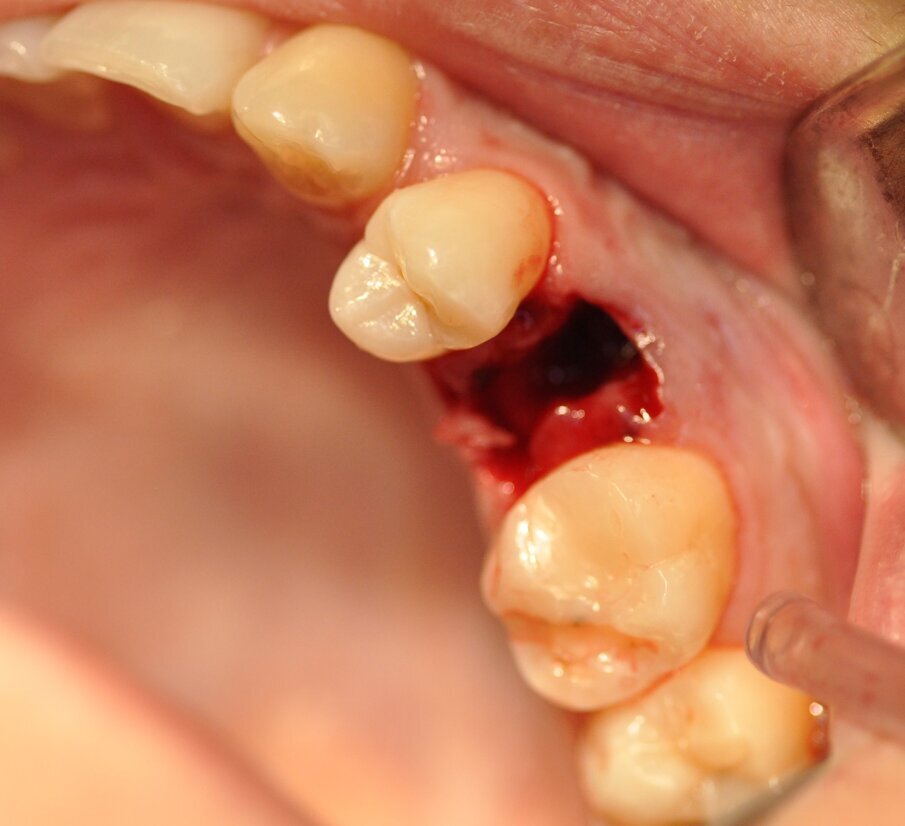

La paziente presentava un primo premolare superiore sinistro non recuperabile. La CBCT mostra la situazione iniziale (Fig. 1). Si noti quella che appare come una grande fenestrazione buccale nell’area della resezione radicolare (Fig. 2). Il dente fratturato è stato estratto (Figg. 3, 4). Lo scollamento del lembo di accesso rivela la fenestrazione buccale (Fig. 5). L’osteotomia è stata preparata secondo il protocollo di fresatura di Neoss ProActive Edge (Fig. 6). Successivamente viene posizionato un impianto Neoss ProActive Edge Ø 5.0 × 13 mm (Fig. 7). L’impianto è stato posizionato in una situazione di disponibilità ossea molto limitata e densità ossea media (Fig. 8). Nonostante le limitazioni dovute alla condizione ossea, è stata raggiunta una buona stabilità primaria. È stato utilizzato un torque di inserimento di 20 Ncm, l’ISQ è risultato in un range di 70/77. Per correggere la fenestrazione buccale è stato eseguito un innesto con particolato osseo di origine porcina (Fig. 9). L’innesto osseo è stato coperto con una membrana di collagene riassorbibile (Fig. 10). Il lembo mucoso è stato suturato attorno al pilastro di guarigione in PEEK, consentendo la guarigione in una sola fase (Fig. 11).